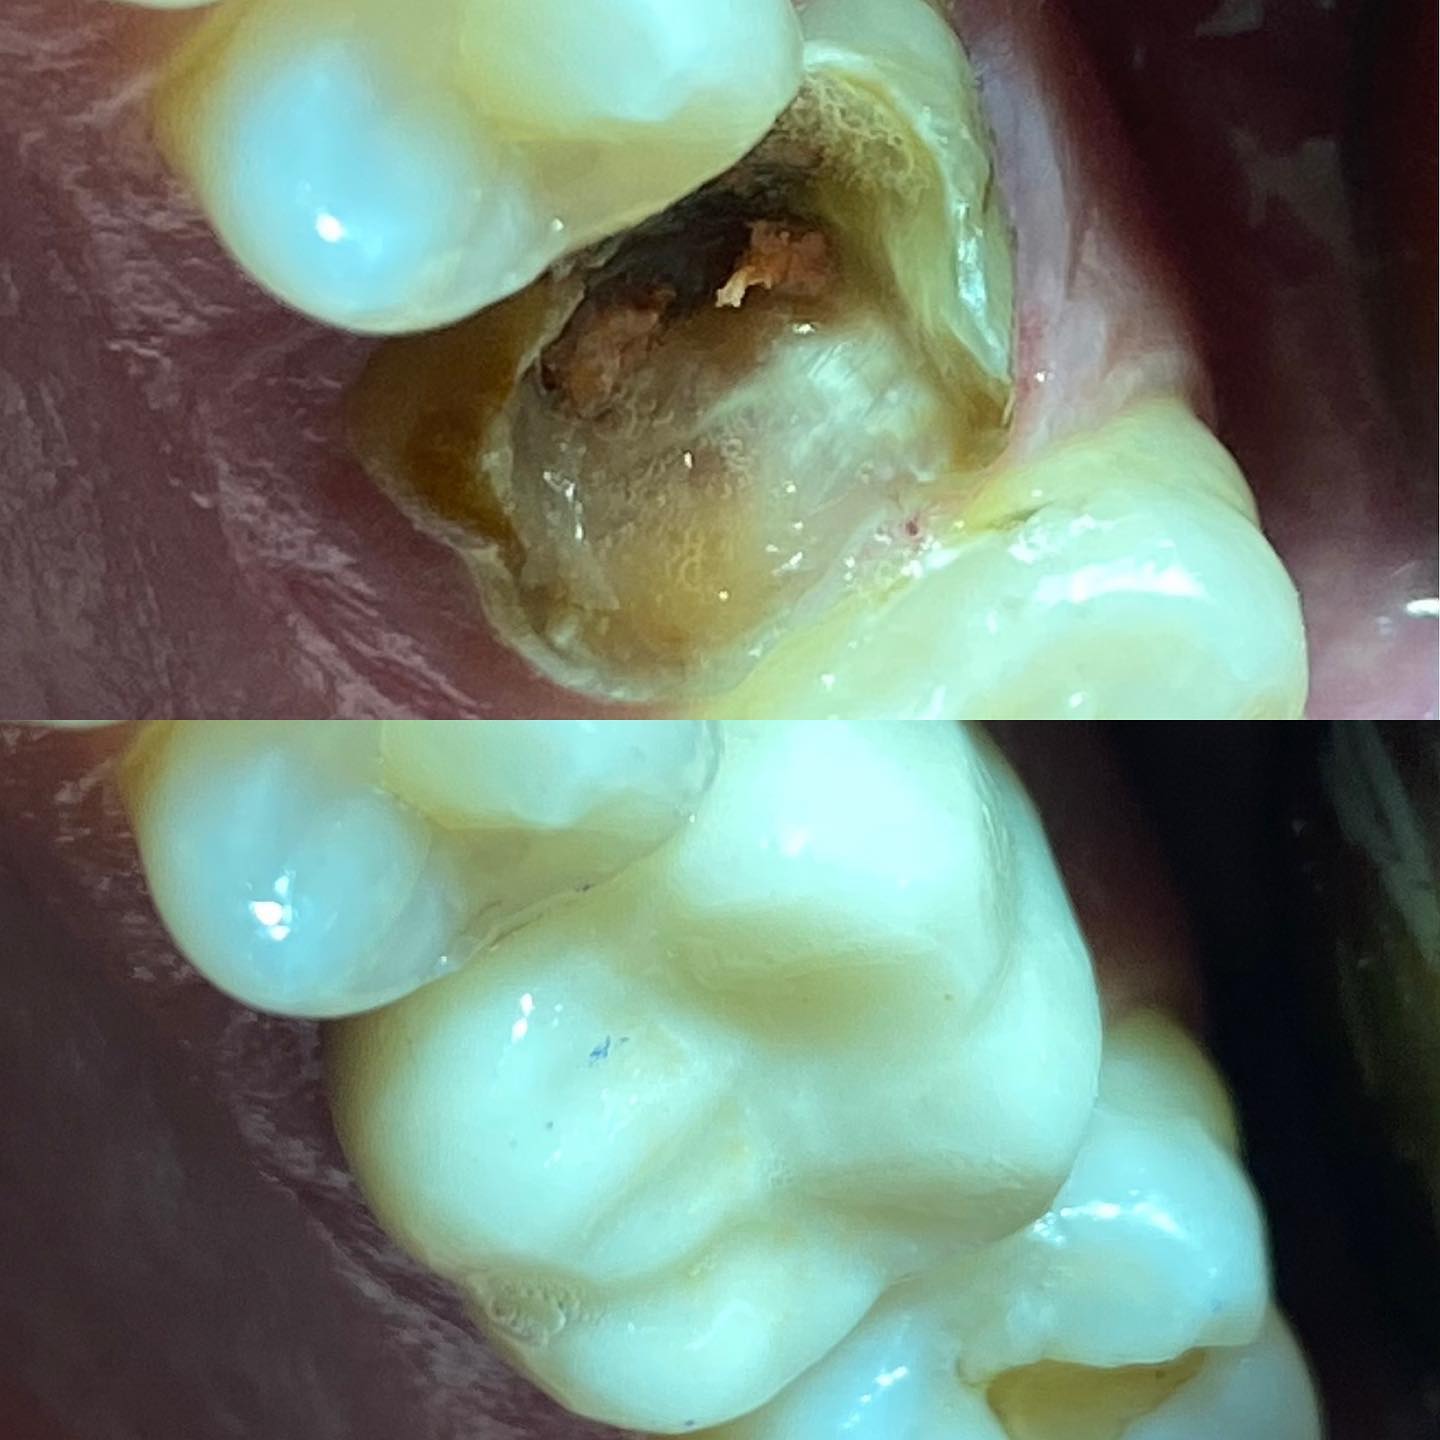

Galeria

Confira nossa galeria de fotos e veja como transformamos sorrisos, promovendo saúde e bem-estar aos nossos pacientes.